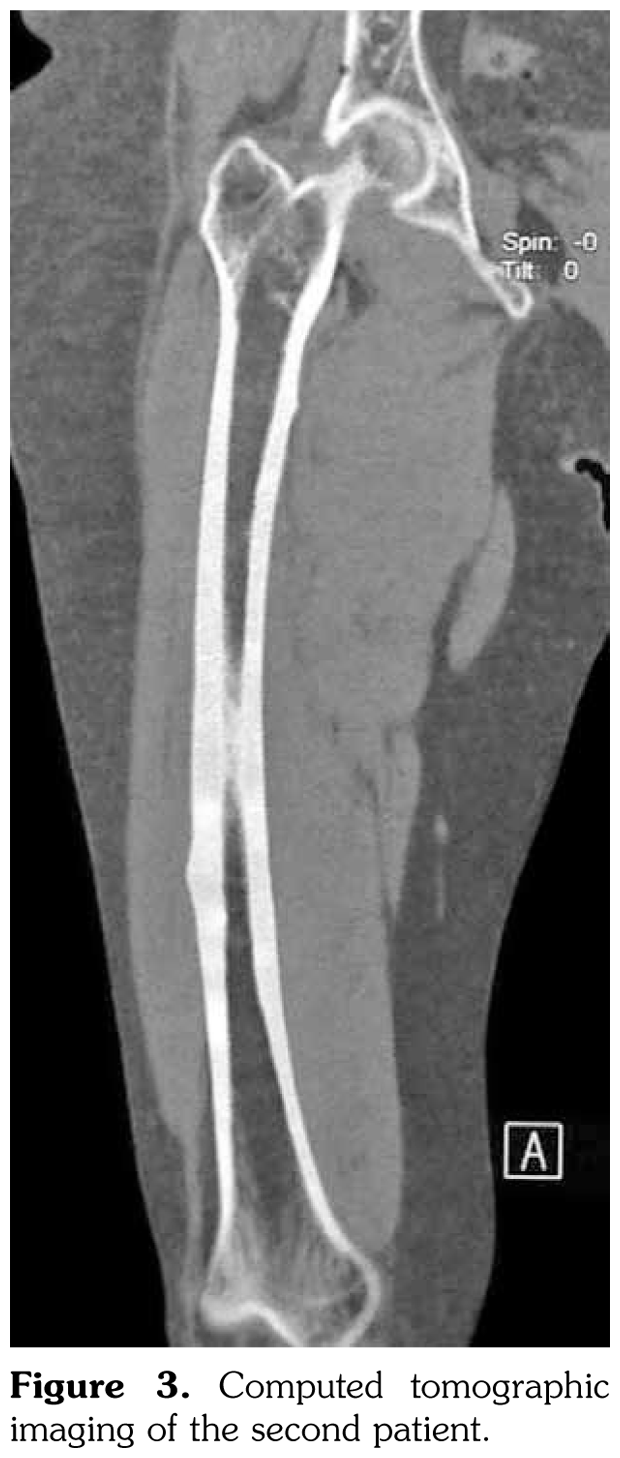

Case 2– A 61-year-old female patient presented with anterior thigh pain and difficulty in walking. Pain severity was 7 over 10 point according to visual analog scale. She had been treated with alendronate 70 mg per week with calcium plus vitamin D for two years. Plain radiographs of femur were taken upon clinical presentation. Cortical stress reaction was detected in both femoral shafts on plain radiographs (Figure 2). Computed tomographic imaging was performed to rule out fracture (Figure 3). Bone scintigraphy showed increased uptake in distal (1)/3 ends of femoral shafts (Figure 4). Serum calcium value was normal and urinary deoxypiridinoline level was mildly increased (46 nM/mMCre).